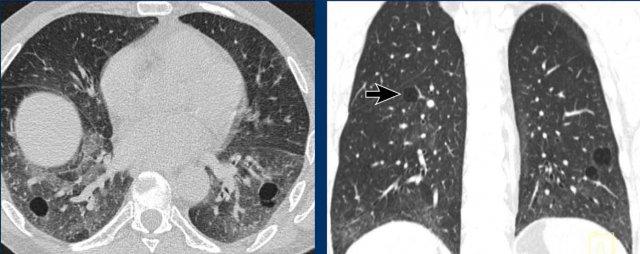

Khí phế thũng

Một số ví dụ về khí phế thũng được đưa vào đây vì khí phế thũng đôi khi có thể mô phỏng hình ảnh bệnh phổi dạng nang.

Hình ảnh

- Khí phế thũng trung tiểu thùy và cạnh vách. Lưu ý sự tương đồng với hình 2, nhưng sự phân bố khác nhau (vùng trên so với vùng dưới) và sự hiện diện của các chấm trung tâm (mũi tên trắng) giúp phân biệt.

- Đây không phải khí phế thũng mà là trường hợp hội chứng Birt-Hogg-Dubé với các nang đơn thuần trong nhu mô phổi và các nang cạnh màng phổi.

- Khí phế thũng cạnh vách.

- Khí phế thũng trung tiểu thùy với dấu hiệu chấm trung tâm (đầu mũi tên đen). Lưu ý sự khác biệt tinh tế so với LCH giai đoạn tiến triển (xem Hình 2 ở phần LCH phía trên), biểu hiện các vách ngăn hoặc thành nang rõ hơn.